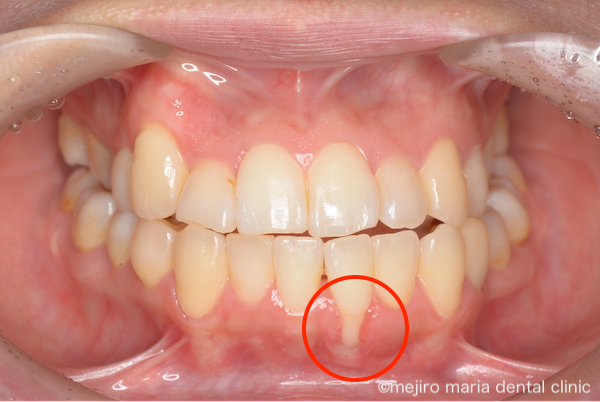

治療前の状態・主訴

この患者様は他院で矯正治療を行い、治療終了後に歯茎が下がってしまったことで(画像赤丸部)、重度の審美的なトラブルと知覚過敏を主訴に来院されました。